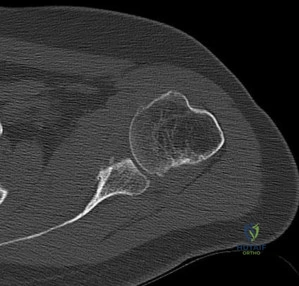

A 24-year-old athlete sustains recurrent anterior shoulder dislocations. An MRI reveals a Hill-Sachs lesion. Advanced imaging and 3D modeling demonstrate that the lesion 'engages' the anterior glenoid rim when the arm is in abduction and external rotation. According to the glenoid track concept, how is this lesion classified?